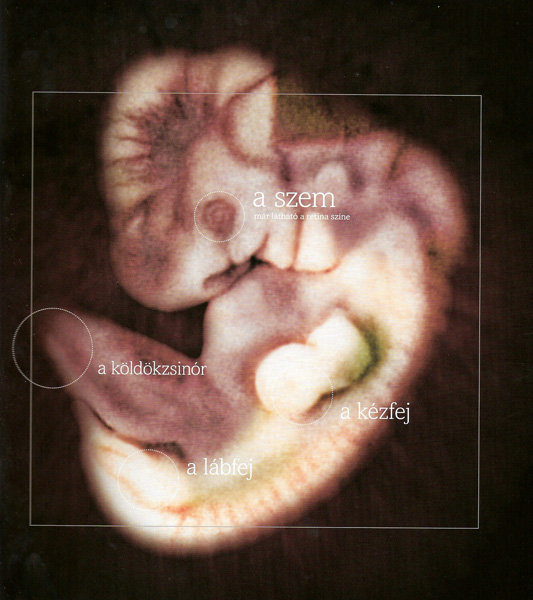

Annus nagyon jók a képek. kis ALien-nek néznek ki... szép az élet...

8 mm a baba  11 mm a baba

11 mm a baba  18 mm a baba